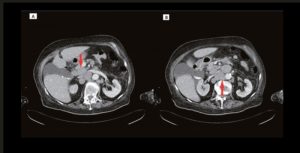

Mme A., traitée par chimiothérapie pour un lymphome non hodgkinien à grandes cellules B est hospitalisée dans le service de médecine aiguë gériatrique pour altération de l’état général.